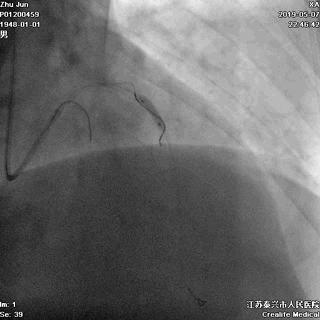

四、STENT植入

---巩固胜利成果

前降支植入第一枚STENT

前降支-左主干STENT定位和植入